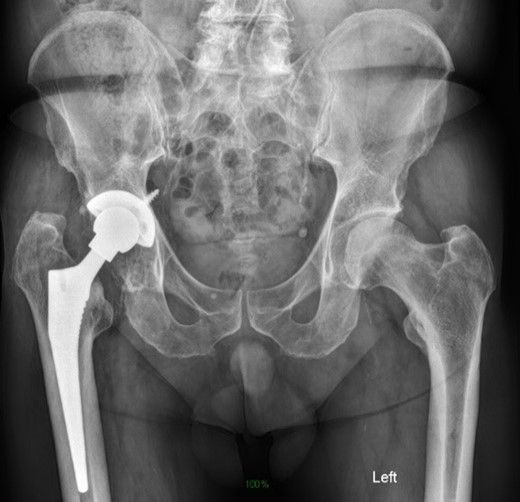

Life-size 3D model was printed from a converted file containing the computed tomography (CT) scan of one patient with severe acetabular defects waiting for total hip revision surgery. The 66-year-old male had a background of coxarthrosis. He underwent total hip arthroplasty of his right hip in February 2017. The preoperative CT scan and X-Ray of the pelvis showed large right-sided pelvic defect and severe acetabular defect (Figs 1 and 2). The patient had history of cardio-vascular comorbidity and underwent 2 week specific antihypertensive therapy preoperatively.

Preoperative radiograph demonstrating large acetabular defect with screw penetration.

The surgery was uneventful and a trabecular metal cup with semilunar augment were implanted (Zimmer, Warsaw, IN). The femur was reconstructed with a cementless Alloclassic stem (Fig. 8)